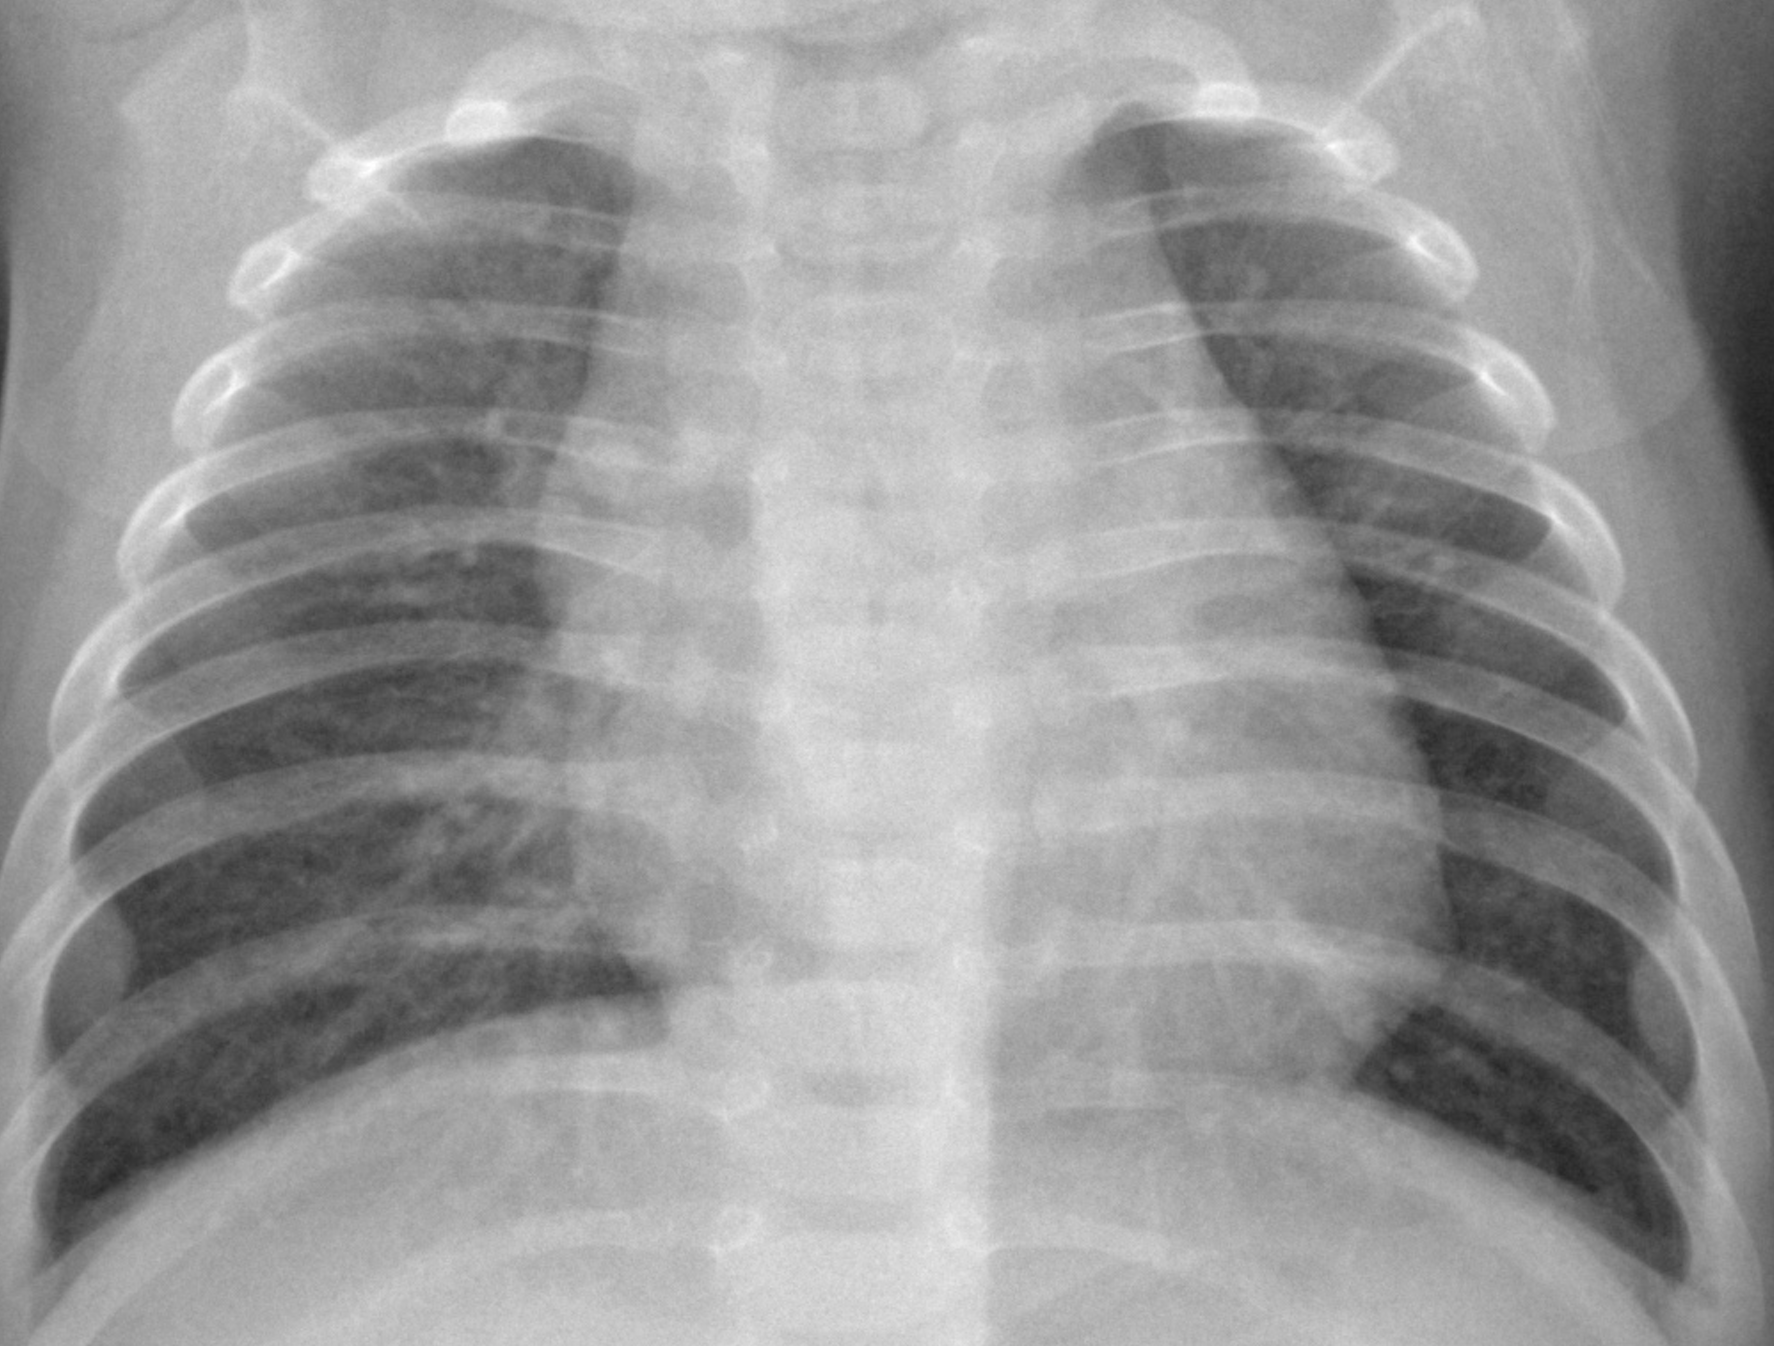

We employ a large-scale of chest X-ray dataset COVIDx [20] to validate the proposed model. It is comprised of 18,543 chest radiography images across 13,725 cases. Example chest X-ray images belonging to normal, pneumonia, and COVID-19 classes from COVIDx dataset are shown in Figure 2. When we examine these examples, we can differentiate these images in terms of features shown within areas marked by the blue circle since we can observe some lighter areas indicating COVID-19 infected regions in the blue circle.

III-D4 Error Analysis

Fig. 6 presents three COVID-19 samples that are classified into Normal, COVID-19, and Pneumonia classes, respectively. X-ray images of COVID-19 patients shows various features for different stages of COVID-19 patients222https://www.uclahealth.orgradiologycovid-19-chest-x-ray-guideline. At the early stage of COVID-19 patients, X-ray images cannot present significant features (Fig. 6 (a)) that can be used to differentiate COVID-19 and Non COVID-19 patients, which leads to the incorrect classification result for the sample. It is consistent with the expectation that X-ray images are not ideal evidences to support diagnosis of COVID-19 for the patients at the early stage.

However, with development of COVID-19, X-ray images are able to present obvious features such as multifocal lung airspace opacities, nodules and consolidation (Fig. 6 (b)), which contributes to the correct classification result. Unfortunately, if the patients are at the late stage of COVID-19, X-ray images presents lobar diffused consolidation (See Fig. 6 (c)) that is similar to features of pneumonia. These features will be confusing to the proposed model and lead to the incorrect result for the sample shown in Fig. 6 (c). In summary, in terms of samples shown in Fig. 6, the proposed model will be effective for the patients who are in the development of COVID-19 rather than those at the early stage or late stage of such disease.